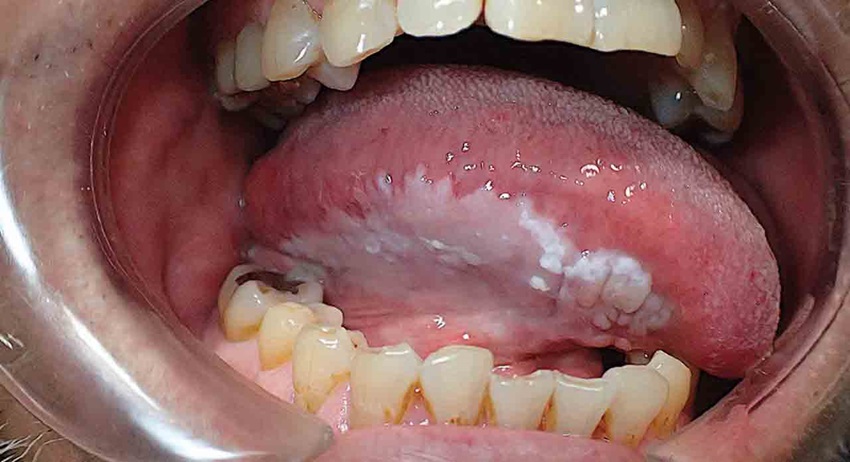

• Bạch sản lông miệng (Oral hairy leukoplakia): Dạng bạch sản này thường do nhiễm HIV/AIDS hoặc virus Epstein-Barr gây ra và tiến triển thành ung thư miệng. Các mảng lông màu trắng, thường xuất hiện ở các nếp gấp trên lưỡi hoặc những khu vực khác trong miệng.

• Bạch sản dạng lông thường xuất hiện mảng lông trắng mờ dạng nếp gấp.